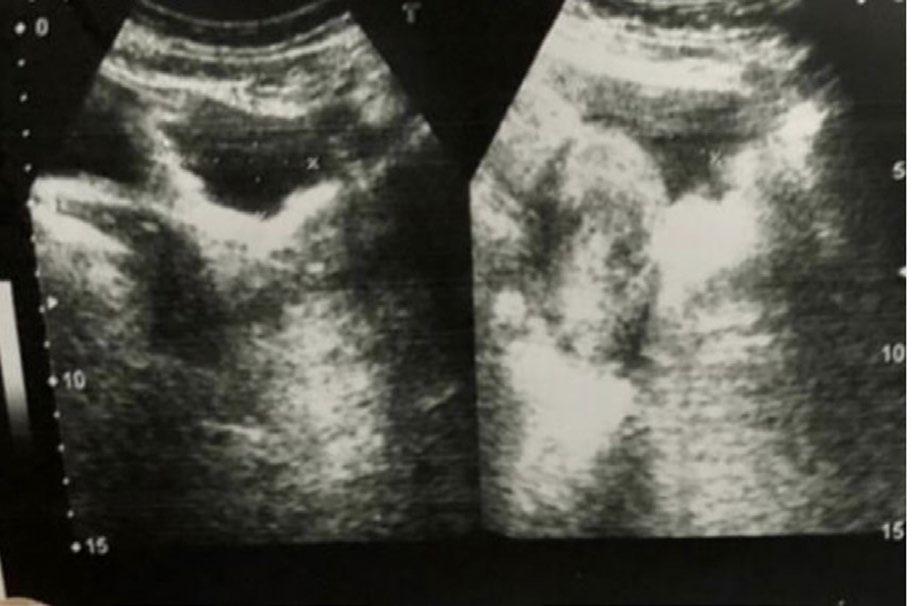

Acute abdominal pain

It is a surgical emergency and needs urgent exploration in the form of either myomectomy or hysterectomy.

Gross pathology

Dark and dusky fibroid due to loss of vascularity

Uncomplicated fibroid

B-mode ultrasound: hypoechoic solid mass with whorled pattern

Colour Doppler: Peripheral vascularity

T1 and T2 hypointense lesion with variable enhancement pattern

Commonly asymptomatic

Patient can be managed both conservatively and surgically. Conservative management includes GnRH agonists and SPRM.

Surgical options include open, hysteroscopic or laparoscopic guided myomectomy or hysterectomy.

Pink in colour

GnRH: gonadotrophin-releasing hormone; SPRM: selective progesterone receptor modulators.

Table 1: Torsed subserosal fibroid versus uncomplicated fibroid.

‘dark fan sign’ is appreciated in the postcontrast sequence, where the uterus adjacent to the twisted leiomyoma shows poor enhancement.1 An increase in the size of the subserosal fibroid on serial imaging with altered perfusion is another clue in the cross-sectional imaging.4 CT can help in diagnosis by demonstrating a twisted vascular pedicle with non-enhancement of the pedunculated leiomyoma. It also rules out other causes of acute abdomen.5

Management of uterine leiomyoma can be both surgical and conservative. It depends on the patient’s age, symptoms, and desire to preserve the fertility, as well as on surgeon’s experience and technology available in the institution. For an asymptomatic uncomplicated uterine leiomyoma various medications like gonadotrophin-releasing hormone agonists or selective progesterone receptor modulators can be used. Surgical options available are open, hysteroscopic, or laparoscopic guided myomectomy or hysterectomy. Minimally